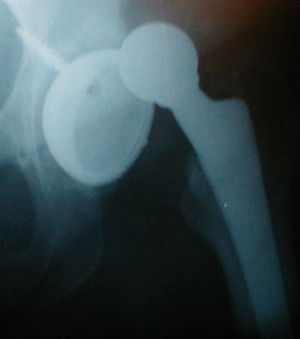

- Hip AP and lateral views

- Posterior Dislocation: AP view femoral head posterior and superior to acetabulum

- If associated femoral neck fracture, will likely need orthopedics

- Consider CT to evaluate acetabulum for subtle fractures (esp for posterior dislocation)